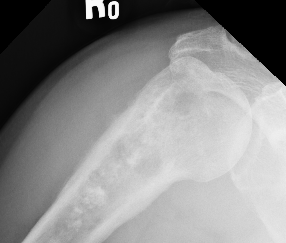

Humerus

1.  Proximal humeral bony tumour

- direct lateral

- through deltoid muscle

- never deltopectoral (condemns patient to forequarter amputation)

2.  Shaft

- modified Henry

- lateral approach

- proximal: through deltoid

- distal: posterior to biceps, through brachialis

OS HumerusHumerus biopsy 2